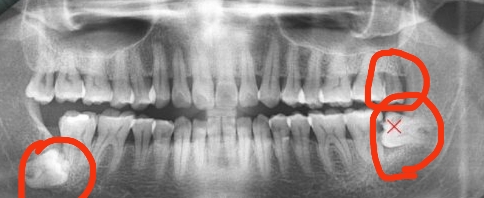

①智慧齒威脅鄰牙:當智慧齒威脅到鄰牙的時候,智慧齒阻生或者生長空間有限,此時應該考慮拔除智慧齒。否則長此以往,鄰牙可能被擠歪頂壞,出現一系列後遺症。因此此時智慧齒應該考慮拔除。

④智慧齒埋伏生長:當智慧齒完全不能生長出來,此時可以考慮拔除。